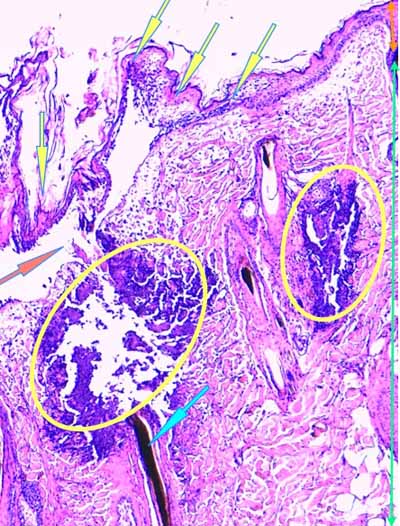

Photo 13 (Hémalun-Eosine X200) : dans le derme, on remarque des plages

cellulaires inflammatoires, peuplées de granulocytes neutrophiles,

en étroit rapport avec les unités annxielles folliculo-sébacées.

Légendes de la Photo 13 :

- Étoiles rouges vides : glandes sébacées

- Étoiles rouges pleines : follicules pileux

- Pointe de flèche jaune : canal pilaire

- Flèches turquoises : plage cellulaire inflammatoire peuplée de cellules pycnotiques et de granulocytes neutrophiles

- Double flèche verte : derme

Photo 14 (Hémalun-Eosine X100) : à la jonction dermo-hypodermique,

un bulbe folliculaire anormal est en rapport direct avec une plage cellulaire inflammatoire.

Légendes de la Photo 14 :

- Étoile rouge vide : adipocyte

- Étoiles rouges pleines : vaisseaux sanguins (une erreur au milieu à droite = adipocyte)

- Pointe de flèche jaune : reliquat de bulbe pilaire fracturé et désolidarisé du reste du follicule pileux

- Flèches turquoises : plage cellulaire inflammatoire peuplée de cellules pycnotiques et de granulocytes neutrophiles, en étroit rapport avec le reliquat de bulbe folliculaire

- Double flèche bleue : hypoderme